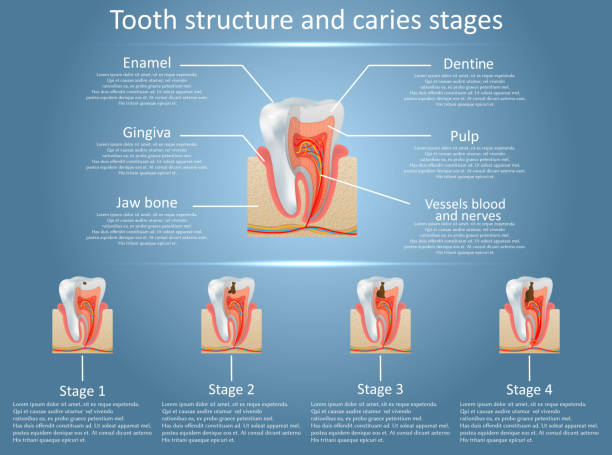

خب، اول از همه #عصب_دندان چیه؟ تصور کن یه شبکه پیچیده از رشتههای عصبی توی ریشه دندونت وجود داره. این عصبها مسئول حس کردن درد، دما و فشار هستن. وقتی دندونت دچار پوسیدگی عمیق، شکستگی یا ضربه میشه، این عصبها ممکنه آسیب ببینن و التهاب کنن. حالا چرا این موضوع مهمه؟ چون اگه عصب دندان آسیبدیده درمان نشه، میتونه باعث درد شدید، عفونت و حتی از دست دادن دندون بشه. درد عصب دندان مثل یه آلارم خطر میمونه که بهت میگه یه مشکلی وجود داره و باید بهش رسیدگی کنی.

به عبارت دیگه، عصب دندان نقش حیاتی توی حفظ سلامت و عملکرد دندون داره. اگه این عصب نباشه، دندون دیگه حس نداره و ممکنه بدون اینکه متوجه بشی، دچار آسیب بشه. پس مراقبت از عصب دندان و درمان به موقع مشکلاتش، خیلی مهمه. یادت باشه، پیشگیری همیشه بهتر از درمانه! پس با رعایت بهداشت دهان و دندان و مراجعه منظم به دندانپزشک، میتونی از سلامت عصب دندونت محافظت کنی.

یه نشونه دیگه، حساسیت دندونه. اگه دندونت به سرما، گرما یا شیرینیجات خیلی حساس شده، ممکنه عصب دندونت تحریک شده باشه. البته حساسیت دندون همیشه به معنی آسیب دیدگی عصب نیست، اما بهتره یه بررسی بشه. تورم و التهاب لثه اطراف دندون آسیبدیده هم میتونه نشونهای از مشکل عصب دندون باشه. در بعضی موارد، ممکنه دندون تغییر رنگ بده و تیرهتر بشه. این تغییر رنگ معمولا به خاطر خونریزی داخل عصب دندون اتفاق میافته.

با استفاده از یه سری ابزار کوچیک و ظریف، دندانپزشک عصب آسیبدیده و بافتهای مرده داخل کانال ریشه دندون رو خارج میکنه. این مرحله خیلی مهمه، چون اگه عصب به طور کامل خارج نشه، ممکنه عفونت دوباره برگرده. بعد از اینکه کانال ریشه دندون تمیز شد، دندانپزشک اون رو با یه ماده مخصوص به نام گوتاپرکا پر میکنه. این ماده از ورود باکتریها به داخل کانال ریشه جلوگیری میکنه.